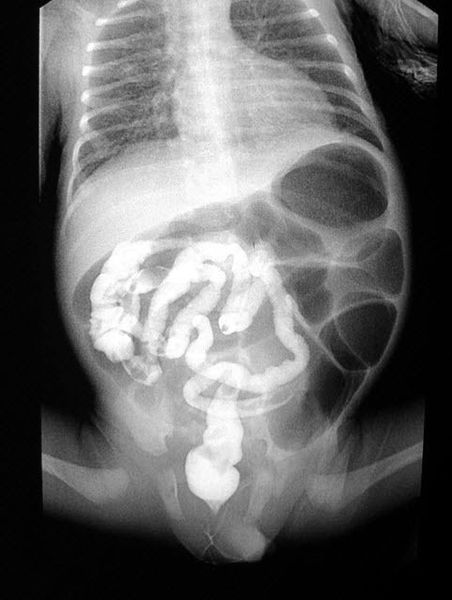

Обзорную рентгенограмму брюшной полости проводят для выявления вздутых петель кишечника и признаков кишечной непроходимости. При осмотре может быть обнаружено увеличение печени (гепатомегалия). Также у пациентов выявляют сахарный диабет I типа, который сочетается с респираторными симптомами: одышкой, частым кашлем с трудноотделяемой вязкой мокротой и панкреатитом, проявляющимся опоясывающими болями в области живота и частым стулом непереваренной пищей.

![Рентгенограмма брюшной полости при муковисцидозе [16] Рентгенограмма брюшной полости при муковисцидозе [16]](/media/bolezny/mukoviscidoz/rentgenogramma-bryushnoy-polosti-pri-mukoviscidoze-16_s.jpeg?dummy=1757926469893)

Рентгенограмма брюшной полости при муковисцидозе [16]